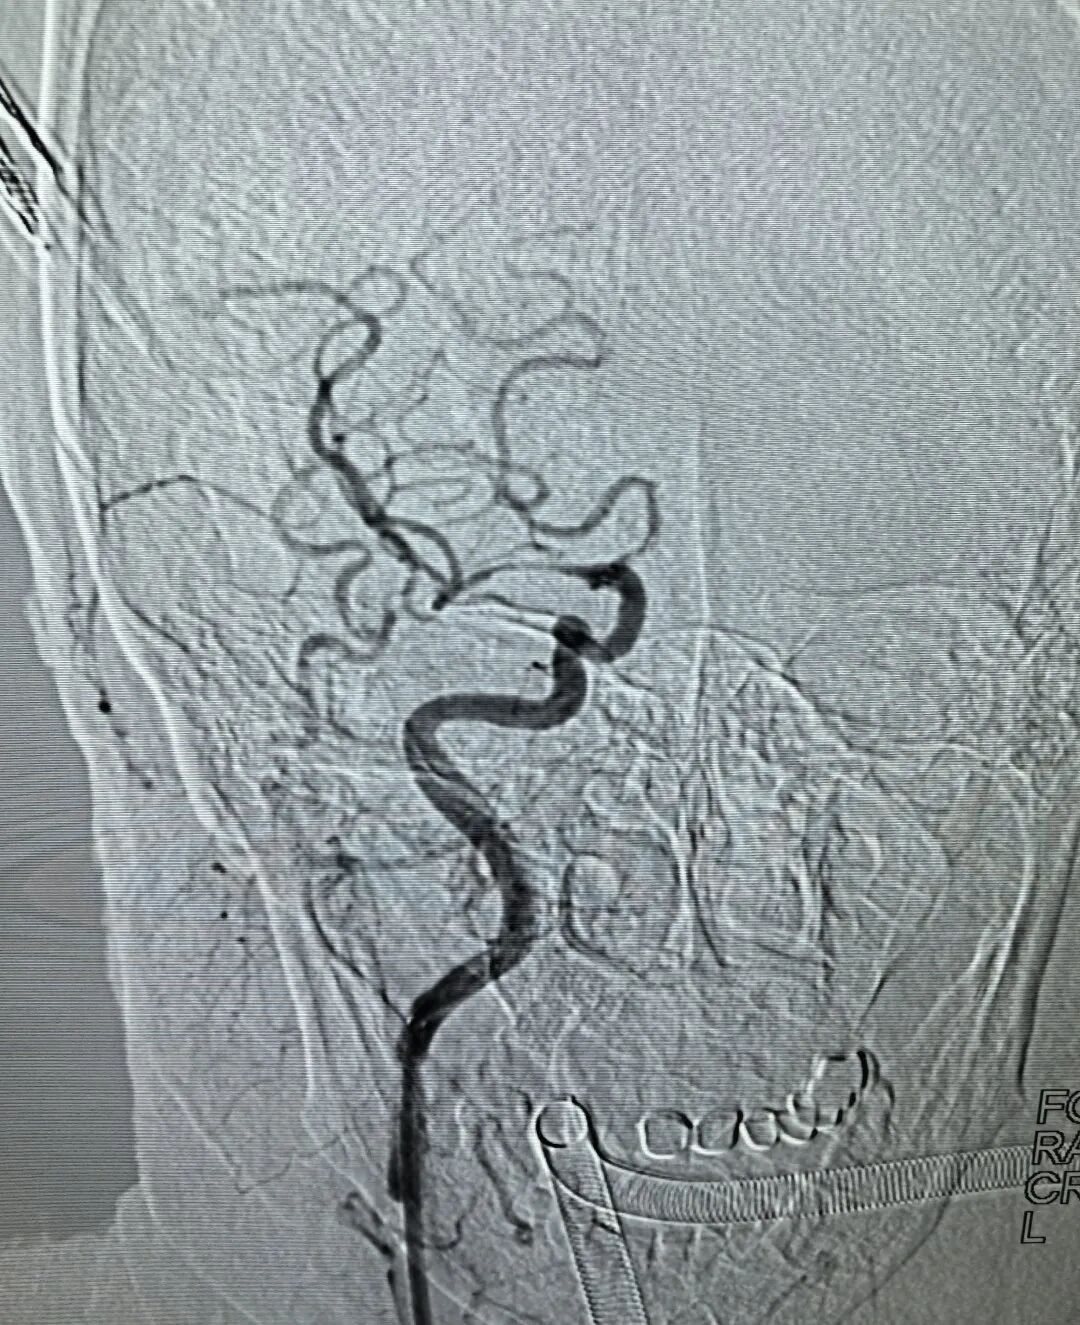

【技术领航】大脑中动脉“极细段”遭遇顽固血栓!市二院神经介入科精准取栓成功救治急性大面积脑梗死危重患者!

“精湛医术保健康,高尚医德为患者”!近日,一面承载着患者全家深深感激的锦旗,被赠送到葫芦岛市第二人民医院神经介入科钟强主任及陆阔医师手中。锦旗背后,是一场与死神赛跑的生命奇迹,钟强主任团队凭借高超的神经介入技术与多学科无缝协作,成功为一名急性大面积脑梗死危重患者施行高难度取栓手术,打通了被顽固血栓“死死封堵”的极细血管,最终助力患者获得良好康复。

挑战极限:“绣花功夫”疏通“生命狭道”